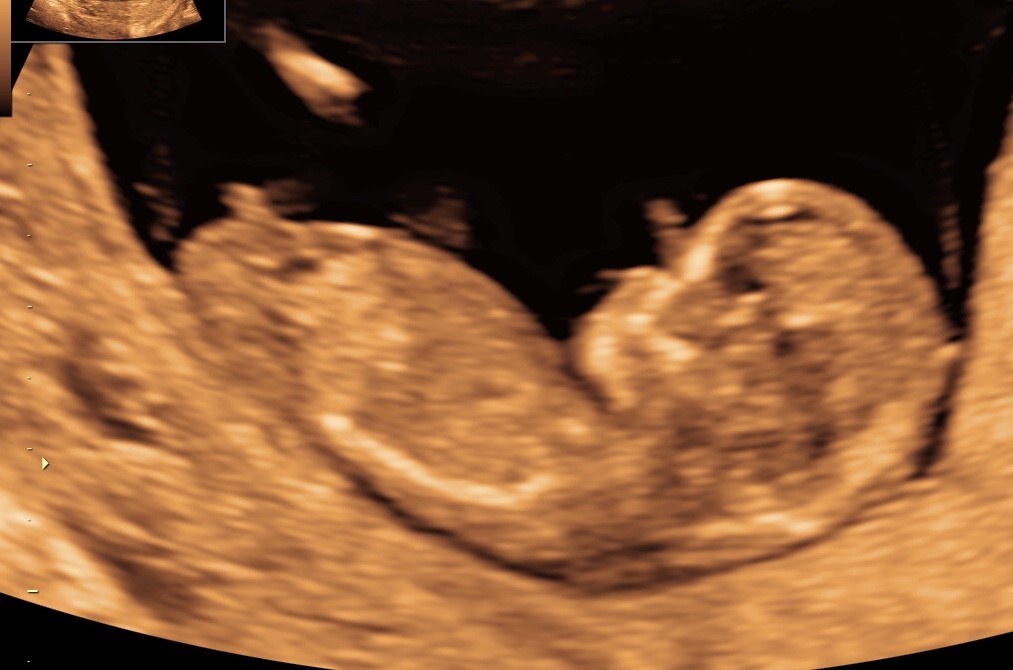

Nogen som har et gæt?

Vi skal ikke vide kønnet, men kunne være sjovt at høre hvad folk tror.. Scanningen er lavet 12+1

Vedhæftede fotos (klik for at se i fuld størrelse)